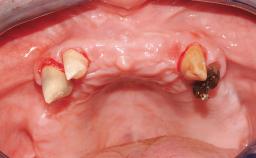

Early Loading of Two Implants in the Mandible and Final Restoration with a Retentive-Anchor-Supported RDP

A 63-year-old male edentulous and maladaptive patient presented with an inability to wear his existing complete maxillary and mandibular dentures. He had been edentulous for 41 years, and there had been three unsuccessful attempts by dentists to provide complete dentures for him. Efforts to wear both complete dentures were always initially encouraging, but over time, he invariably found that he was unable to wear the complete mandibular denture, and this pattern had persisted for 20 years. After seeing local newspaper advertisements, he requested having his complete mandibular denture stabilized with implants.

Case Type Edentulous Mandible

Area Full-Arch

# of Teeth All